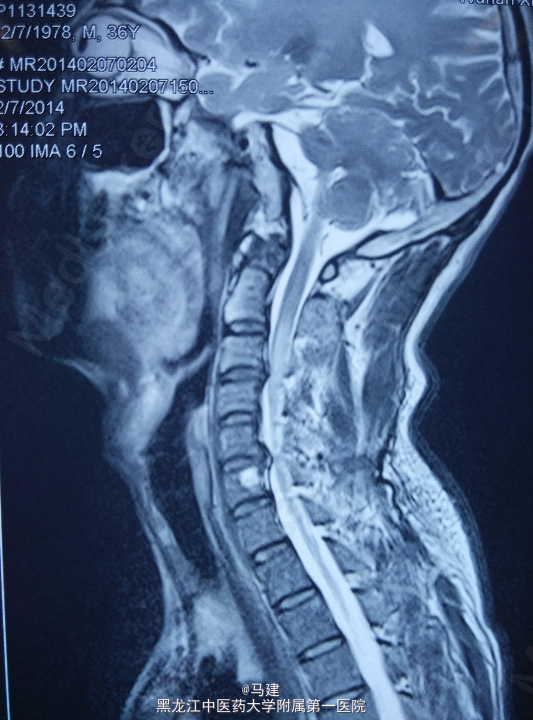

5号患者,男,36岁 主诉:颈椎骨折术后15月余 现病史:患者于2014年2月因摔伤后颈椎骨折收入我院,术前患者行走困难,肩上抬无力,双手手指屈伸障碍,无法下蹲,四肢感觉无明显异常。入院后行脊椎后路减压+侧块钉+椎弓钉固定术后上述症状明显改善,术后现诉双手拇指、示指及脚板轻度麻木。 余无明显异常。

查体心肺腹未见明显异常。 专科情况:颈椎曲度存在,外形正常,各棘突无压痛、叩击痛。双上肢肌力正常,拇指、示指轻度麻木,其余各指感觉,双上肢运动正常,末梢血运可。双下肢肌力正常,感觉、运动可。 实验室检查:血常规、生化指标及凝血功能未见明显异常。

初步诊断:1、颈椎骨折术后; 2、颈椎间盘突出